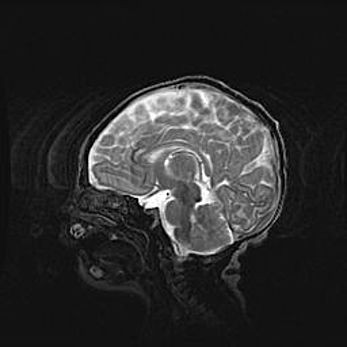

Аномалия Денди-Уокера. Признаки гипоплазии мозолистого тела.

Возраст: 5 месяцев 3 дня

Вес: 5550 г

Пол: мужской

Окружность головы: 39 см

Срок гестации: 40 недель

Аномалия Денди-Уокера – это порок развития головного мозга, для которого характерна триада симптомов: гипотрофия или аплазия червя мозжечка и/или полушарий мозжечка, расширение четвёртого желудочка с формированием ликворной кисты задней черепной ямки, гипертензионная гидроцефалия различной степени.

Гипоплазия мозолистого тела относится к дефектам внутриутробного этапа развития мозговой ткани, возникающим в процессе закладки структур головного мозга, что происходит на начальных этапах развития эмбриона.